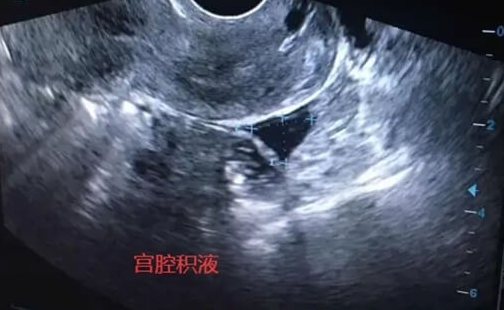

宫腔积液对试管婴儿成功率有一定影响。少量积液可能自行吸收,但大量积液可能改变宫腔环境,影响胚胎着床和发育,甚至导致流产。因此,发现宫腔积液后,医生通常会建议暂停胚胎移植,通过B超监测积液量及性质,必要时进行宫腔镜检查,明确原因并针对性处理,如控制炎症、改善宫腔粘连等,待宫腔环境恢复正常后再进行移植,以提高成功率。